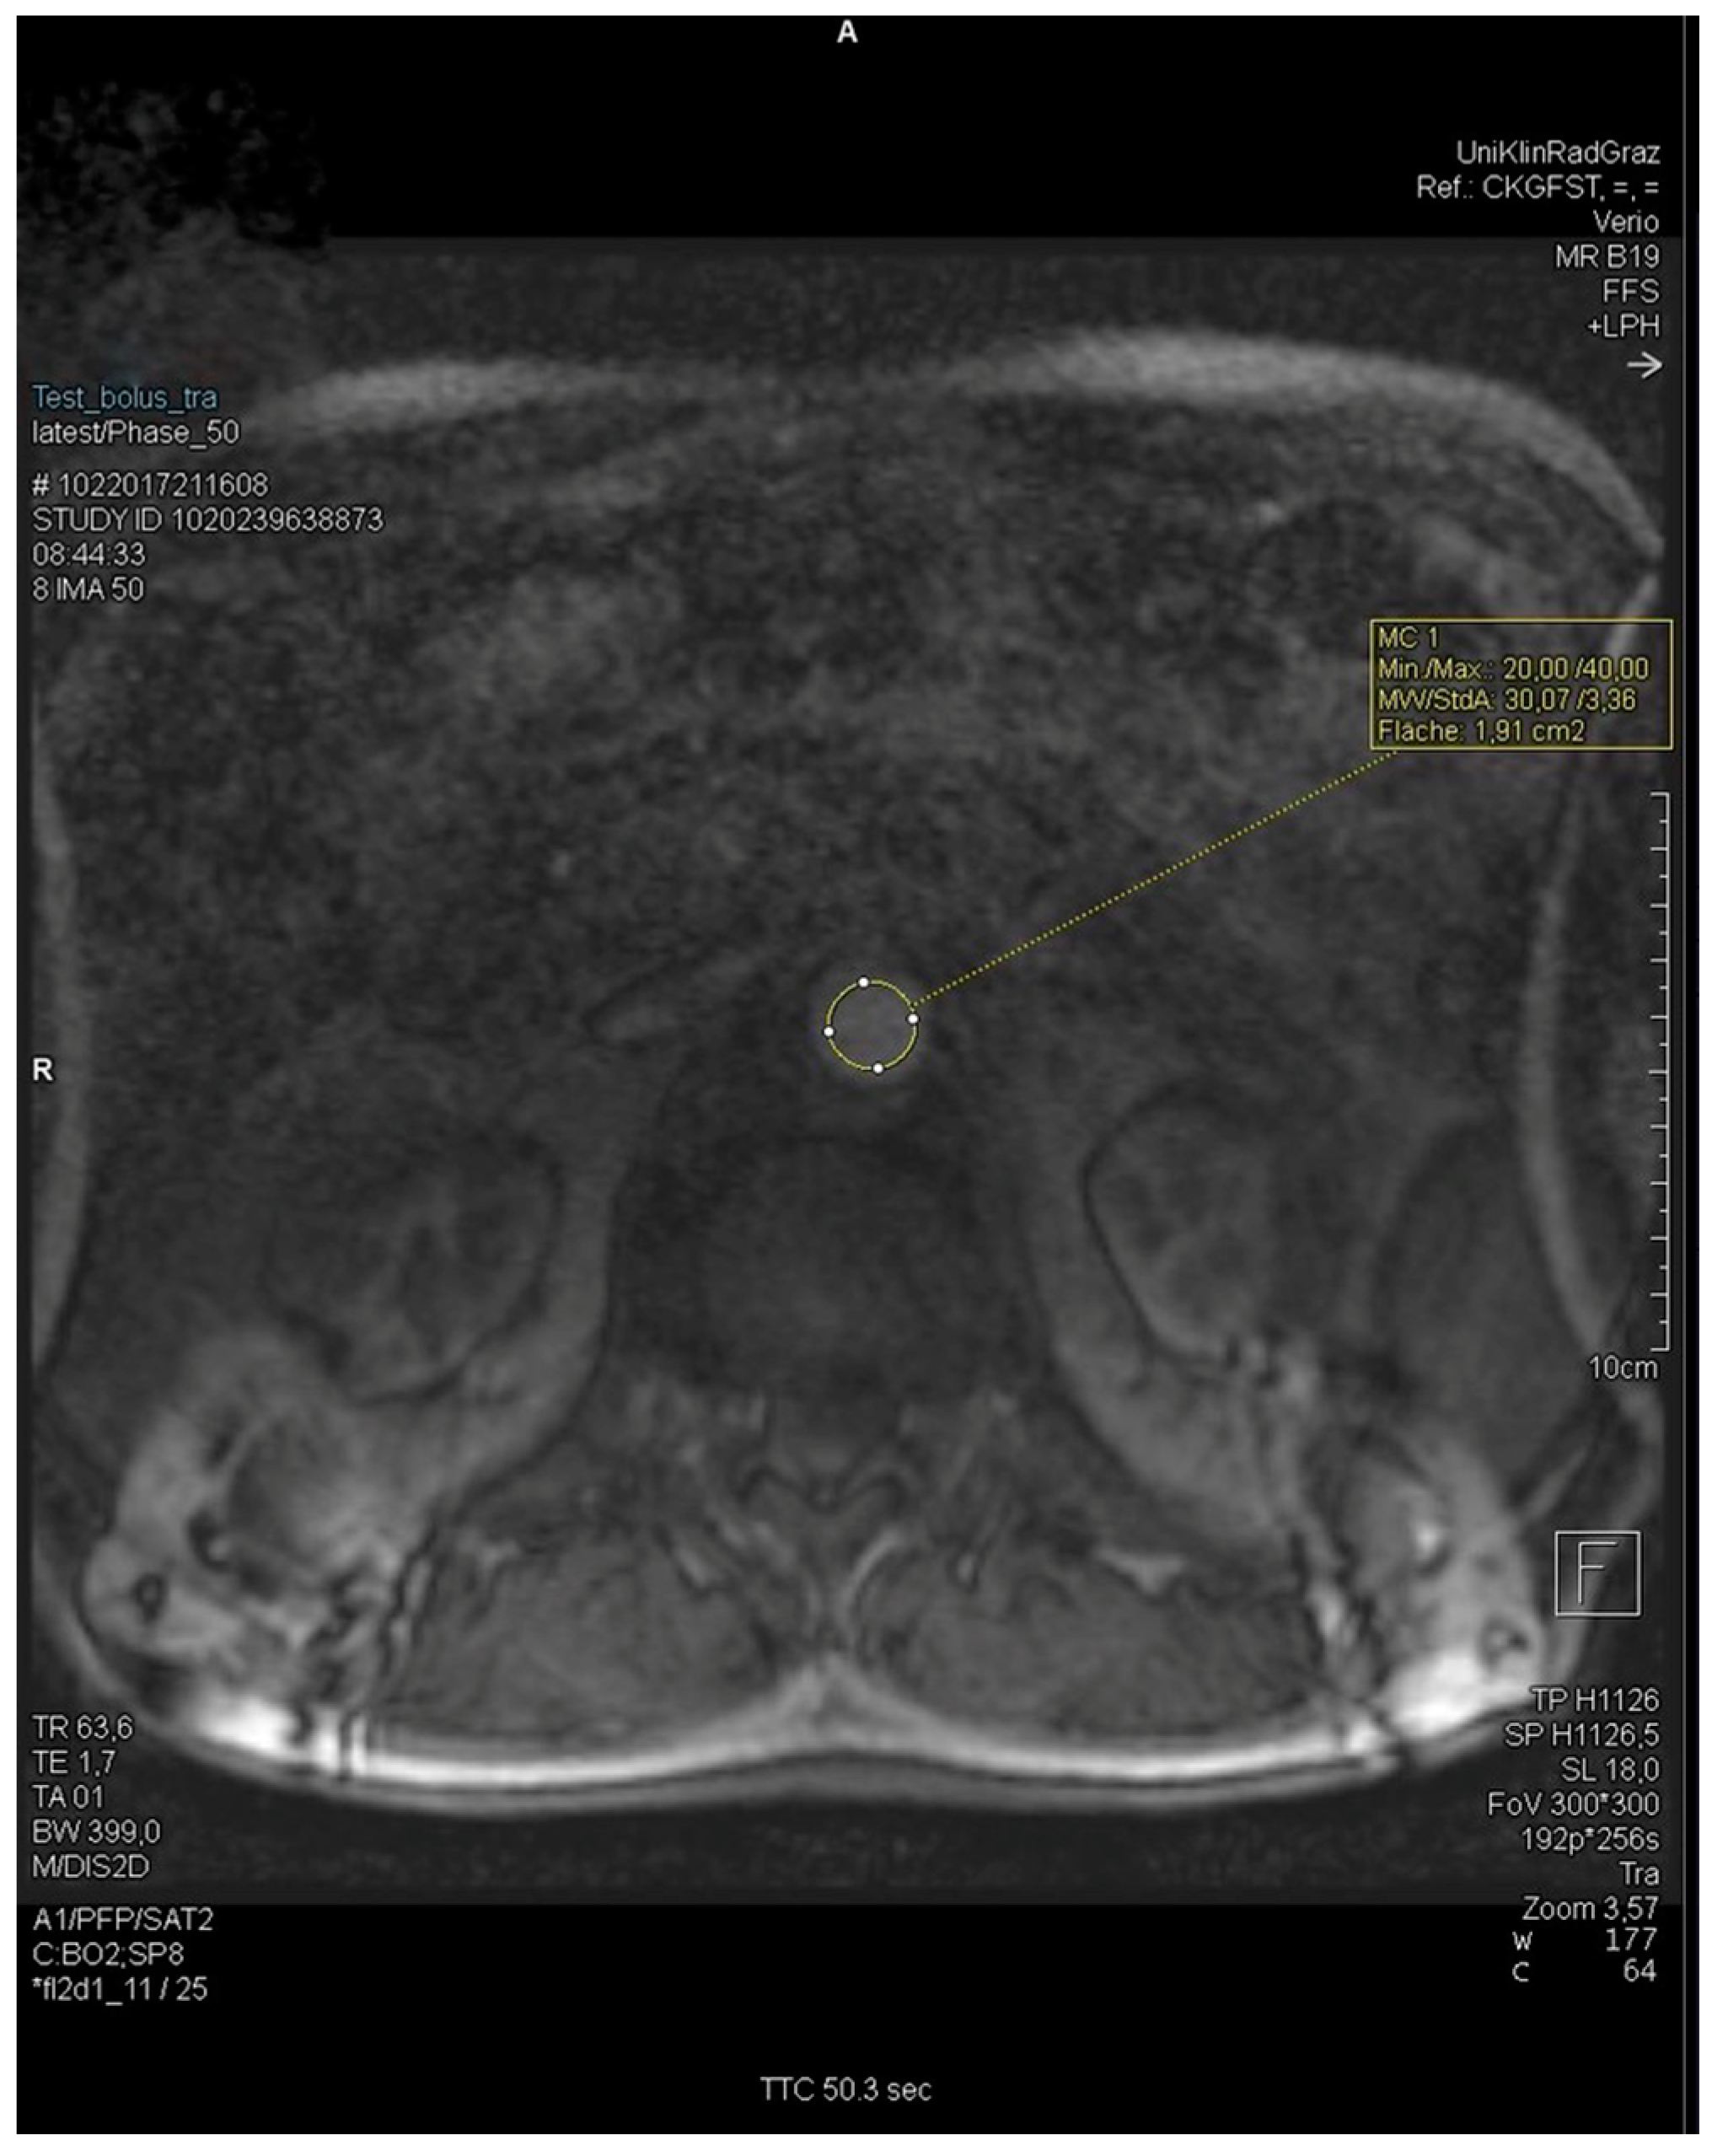

After establishing intravenous access and correctly positioning the patient in the MRI machine, the injection pump filled with contrast media is connected to the IV access. For CE-MRA, the “MEDRAD® MRXperion” (MEDRAD® MRXperion MR Injection System; Bayer Healthcare, Whippany, NJ, USA) injection pressure pump is used. Initial images are taken without contrast media for a preliminary overview of the body regions. In total, 1–2 mL of contrast media; 0.5–1 mmol/mL gadolinium with 0.5–2 mL/s flow; 30 mL saline 0.9% flush was used. The infusion pump is activated at a flow rate of 1.0 mL/s, 1.5 mL/s, or 2 mL/s, and simultaneously, a sequence of images from the abdominal aorta is captured every second. After 60 to 90 s, the image sequence capture is stopped. The ROI (region of interest) for determining the delay is located over the bifurcation of the abdominal aorta into the right and left common iliac arteries at the level of the kidneys or the branching of the renal arteries (Figure 1). The resulting graph shows the signal intensity’s rise, peak, and fall over time (Figure 2). The maximum signal intensity, defined as the TTP, is used as the delay time for the actual angiography. The TTP value is the peak measured by the graph.

Figure 1.

MRI of ROI set in the abdominal aorta at kidney level.

2.4.2. Test Bolus and Measurement

In MEDOCS®, the delay was documented and recorded either in the documents of the radiology technicians or as part of the scanned protocols. If the test bolus was sent and saved as an image sequence with the MR images, the test bolus graph could also be analysed. The syngo.via® workstation (Siemens®) was used to analyse the TTP, full-width half-maximum (FWHM) time, and the time the continuous signal increase began. For better readability, the start of the continuous signal rise is referred to below simply as “signal start.” The height of the test bolus image sequence limited the plane of the ROI in the transverse section. For coronary sectioning, the ROI was set at the level of the kidneys and caudal to the renal arteries. An example of the ROI set in the abdominal aorta is shown here. Figure 1 shows the ROI at the level of the kidneys due to the transverse plane.